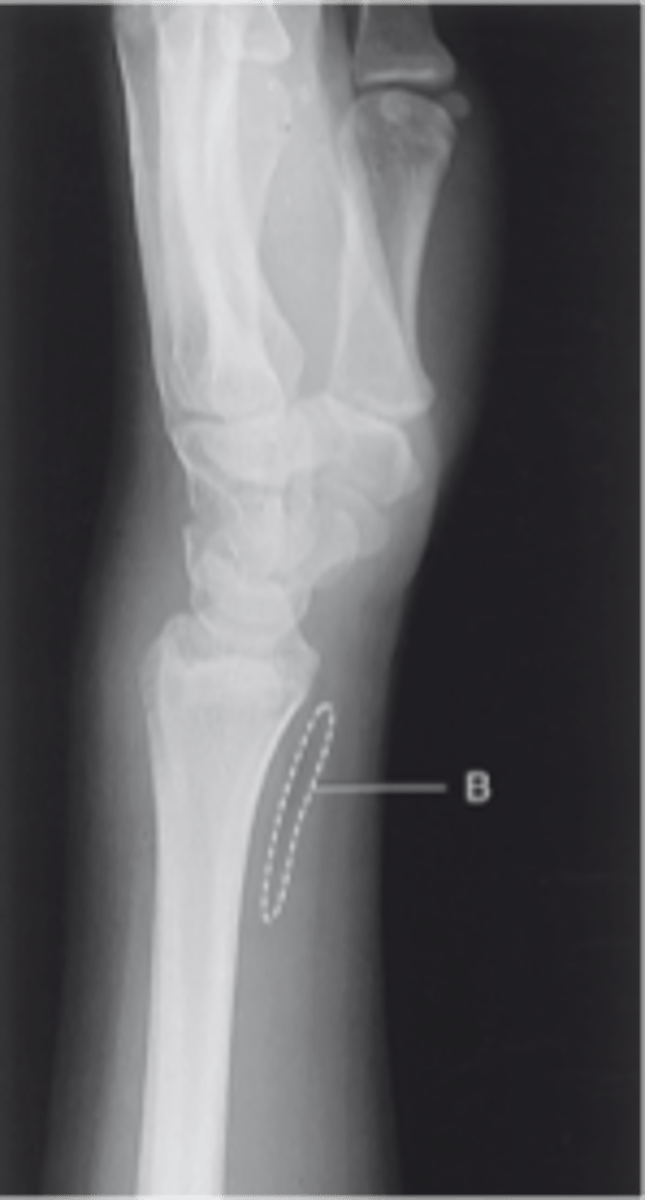

Lateral wrist

pronator fat stripe